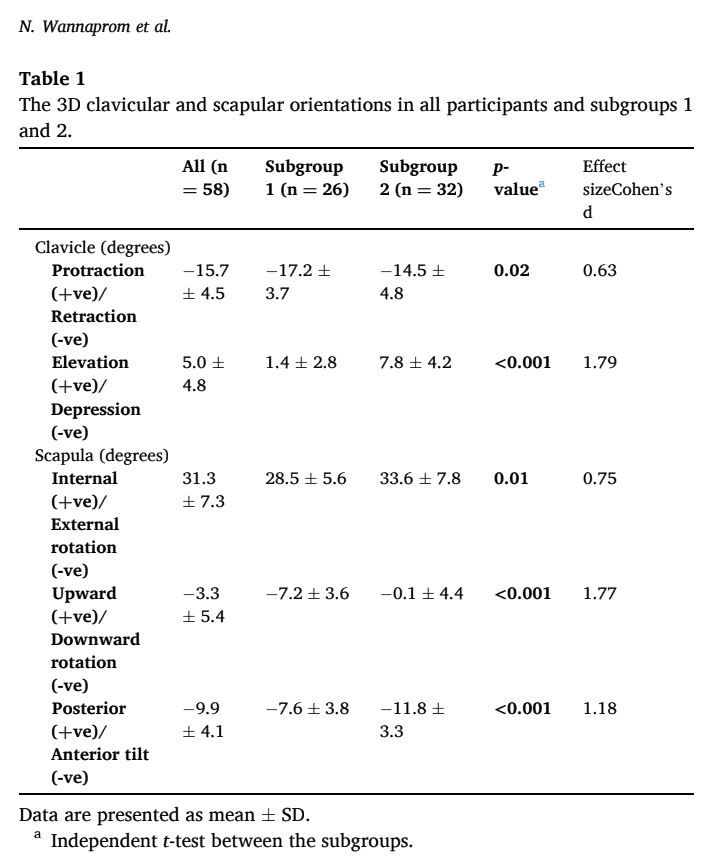

根据 3D 测量结果确定了两个分组。 在分组 1 中,参与者的锁骨回缩和肩胛骨下旋幅度更大。 在亚组 2 中,锁骨隆起增加,肩胛骨更加前倾和内旋。 第 1 分组更经常报告头痛,上颈部或整个颈部的疼痛更严重,而第 2 分组报告的疼痛更多发生在下颈部。 在所有其他结果(人口统计学、颈部疼痛强度、持续时间和残疾程度)方面,各亚组的结果相同。

考虑到颈部疼痛患者对肩胛骨复位的反应,本研究发现,88.5% 的亚组 1 参与者做出了积极反应,而亚组 2 中的 81.2% 没有做出积极反应。

这项研究的一个优点是提供了很多细节,而这些细节是重现这项试验所必需的。 我们有兴趣看看随机对照试验对这种肩胛骨复位治疗颈痛得出了什么结论。 但重要的是,这两个亚组在人口统计学、颈部疼痛强度、持续时间和残疾程度方面并无差异。 因此,我们可以假定,除了肩带的解剖学方向和颈部疼痛的位置不同之外,这些人都是非常同质的。 这些分组是根据较大的效应大小确定的。

这项研究根据肩胛骨方向的三维测量结果,在慢性颈痛患者中发现了两个不同的亚组。 肩胛骨向下旋转和锁骨内收较多的一组对肩胛骨复位有反应,而锁骨抬高、内旋和肩胛骨前倾较多的一组对颈部疼痛的肩胛骨复位无反应。 此外,有反应的人颈部上部疼痛和头痛较多,而没有达到良好反应的人颈部下部疼痛较多。 这可能会对您选择这些患者的治疗方案起到重要作用。